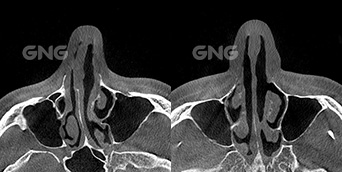

⭐ 비중격 만곡증, 하비갑개 비대,비밸브 협착 40대 남자 환자분으로코막힘 개선을 위해 내원하셨습니다. 내원해서 촬영한 CT를 보면아래쪽의 연골이 거의 90도 이상으로꺾여 있는 것을 확인할 수 있습니다. 수술시에는 이 연골을가운데로 다시 똑바로 세워주는 것이가장 중요합니다. 뒷 부분에서 보면 뼈가 한쪽으로휘어 있는 것이 더 잘 보이는데요. 오른쪽으로 뼈가 . . .